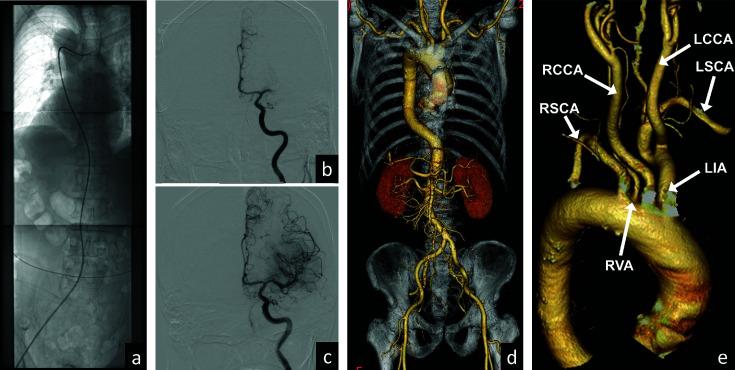

Situs inversus is a rare congenital anomaly which has the mirror image of systemic organs and vessels from their normal position. We report a case of endovascular thrombectomy for acute middle cerebral artery (MCA) M1 occlusion in a patient with complete situs inversus. A right-handed man in his 70s presented to our hospital with loss of consciousness, right-sided hemiplegia, and total aphasia. Endovascular thrombectomy was undertaken for left M1 occlusion. Guide catheter advanced through right aortic arch and injection showed innominate artery was on the left side. Left common carotid artery arose from left innominate artery. Using aspiration catheter and stent retriever, successful recanalization was achieved after three passes. For treatment of acute stroke with large vessel occlusion in patients with situs inversus, understanding anatomy and clinical features of situs inversus is important.

内脏反位是一种罕见的先天性异常,其全身器官和血管的位置与正常位置呈镜像关系。我们报告一例完全性内脏反位患者急性大脑中动脉(MCA)M1段闭塞的血管内血栓切除术病例。一名70多岁的右利手男性因意识丧失、右侧偏瘫和完全性失语入住我院。对左侧M1段闭塞进行了血管内血栓切除术。引导导管经右主动脉弓推进,造影显示无名动脉在左侧。左颈总动脉发自左无名动脉。使用抽吸导管和支架取栓器,经过三次操作成功实现再通。对于内脏反位患者的急性大血管闭塞性卒中治疗,了解内脏反位的解剖结构和临床特征很重要。